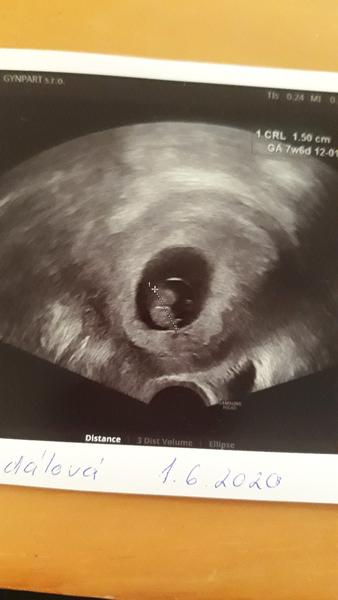

@kostga úplně dobře mi taky není, ale víme, že jak skončí první trimestr tak bude líp, taky chodím do práce a starám se o dceru. A večer, poté co nakonec zaspím dceru již pádem únavou. Jen jsem tak přemýšlela jestli by nešlo nějaké aktivity pro těhotné absolvovat i s malým dítětem. Ale asi ne ... děkuji za tip s foceni, ale já jsem stydlivě a foceni je pro mne noční můrou. Jediné na co jsem zatím přišla, že z každé návštěvy gynekologa si nechám udělat fotku z ultrazvuku. Přeji vsem klidně nekolmplikovane tehotenstvi a zdravá mrňata ....